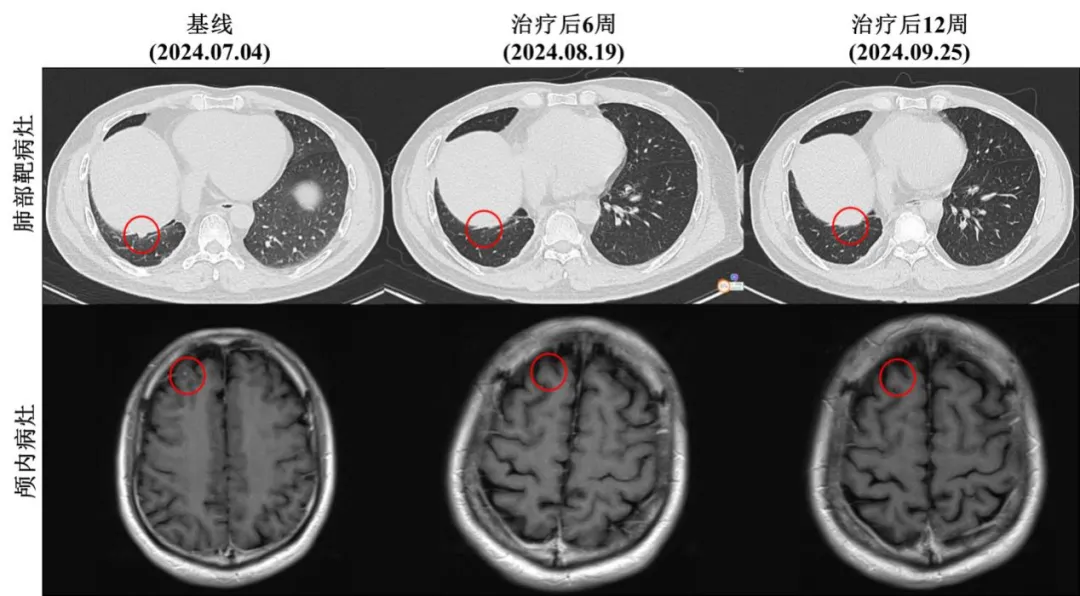

根据最新披露的信息,该研究中有一例ALK阳性晚期NSCLC伴随脑转移的初治患者,在接受Ficonalkib治疗后,所有病灶均实现了完全缓解。

SY-3505(也称CT-3505)是首药控股(北京)股份有限公司完全自主研发的一款第三代ALK激酶抑制剂,是国内首个进入临床研究的国产三代ALK抑制剂。目前,由首药控股(北京)股份有限公司申办的“CT-3505胶囊治疗ALK阳性非小细胞肺癌患者的I/II期临床试验(CT-3505-I-01)”在全国多中心开展,获得良好的效果。以下为郑州大学第一附属医院肿瘤科二病区李醒亚主任团队相关临床研究病例分析: